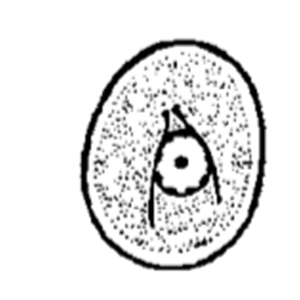

Retortamonas intestinalis cysts are pyriform to ovoid, stain with Lugol and measure 4 to 9 µm long. They have a thin and non-refringent outer membrane and contain one to two nuclei (Euzéby, 2008).